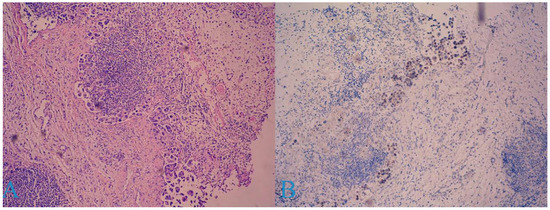

2. Case Report